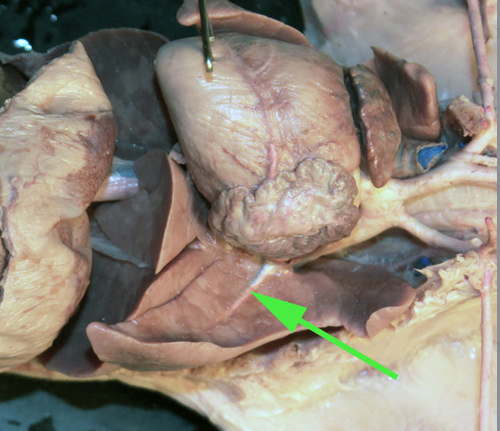

The vessel marked by the green arrow is a coronary artery

The vessel marked by the green arrow is a branch of a pulmonary artery

The vessel marked by the green arrow is a branch of a

pulmonary artery.